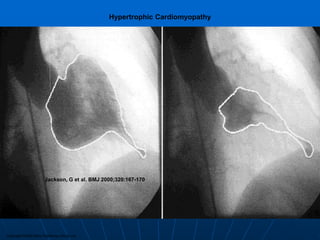

Copyright ©2000 BMJ Publishing Group Ltd.

Jackson, G et al. BMJ 2000;320:167-170

Hypertrophic Cardiomyopathy

Copyright ©2000 BMJPublishing Group Ltd. Jackson, G et al. BMJ 2000;320:167-170 Hypertrophic Cardiomyopathy